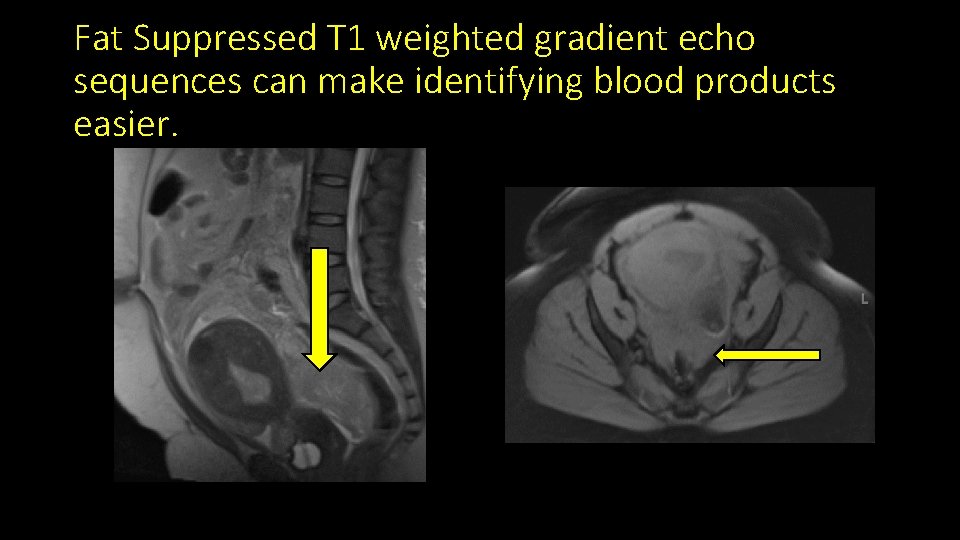

Fat Suppressed T 1 weighted gradient echo sequences can make identifying blood products easier.